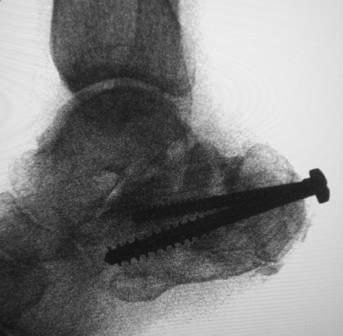

[Ortho] Постравматическая деформация пяточной кости

Уважаемые коллеги.Операция была произведена 22.01.16г. только

сегодня имеется возможность отправить. L-образный доступ. . при ревизии

подтаранный сустав сохранен, поэтому линейная остеотомия, подкожная

ахиллотомия. . подготовка ложа, и смещенный отломок спущен вниз к ложу,

но  до конца не смогли. фиксирован двумя винтами. по медиальной

поверхности рубец плотно спаянный с костной осколькой пока не трогали

из-за опасения инфицирования, после заживления раны потом будем думать

что делать.